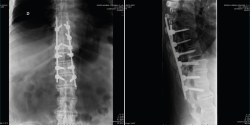

En la Figura 1 se muestra la primera radiografía que le realizan en el centro hospitalario más cercano al accidente. En ella visualizamos un perfil dorsolumbar realizado sobre la camilla de transporte con 2 imágenes. Por un lado, una apertura anterior patológica a través de disco a nivel dorsal, concretamente T10/T11. También observamos una sindesmofitosis de todo el raquis que conocemos como “caña de bambú”. Esto orienta a una enfermedad reumática, concretamente una espondiloartitis anquilosante(1).

Figura 1. Radiografía inicial.